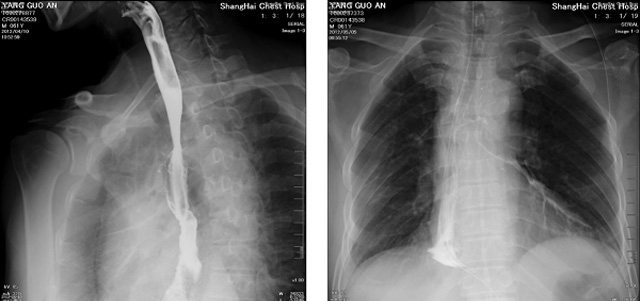

DR设备在2020年的新冠疫情中,加速了市场调整。以医院为主的向二三级市场转变。特别是小巧灵活的移动DR设计,填补CT和磁共振不能三维检查的缺点,满足内科外科特别是骨科的影像诊断需求。还有悬吊DR设备CT断层射线系统。使用锥束成像技术对整个脊柱和整个下肢进行了体积三维扫描。无需使用对比剂,即可使用X射线呼吸功能标测来模拟模拟气流和血流,以评估患者的肺动脉血栓。